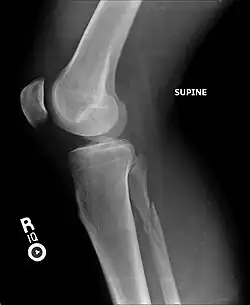

La fracture de Maisonneuve comprend une rupture du ligament deltoïde ou une fracture-avulsion horizontale de la malléole interne, associée à une longue fracture oblique de la fibula (péroné).

La fracture est associée à une déchirure de la partie distale de la syndesmose tibio-fibulaire et de la membrane interosseuse avec parfois une lésion du nerf fibulaire (nerf péronier commun ou nerf sciatique poplité externe) qui passe au niveau du col de la fibula. Cette atteinte du nerf peut entraîner une paralysie de la loge musculaire antérieure de la jambe, d’où l'impossibilité de relever le pied.

La fracture de Maisonneuve est fréquente chez les skieurs et les footballeurs dans les accidents où le pied reste fixé au sol avec rotation externe forcée de la cheville.